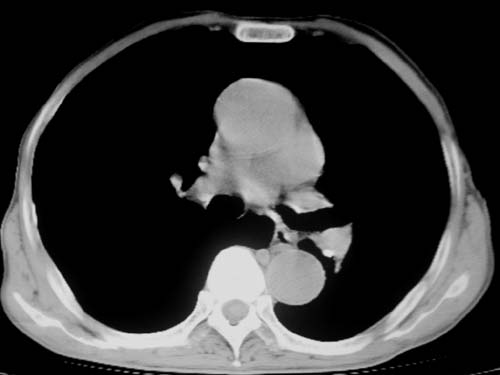

标题: CT19736:男,76岁,咳嗽,胸痛 [打印本页]

标题: CT19736:男,76岁,咳嗽,胸痛

支持左上肺周围型肺癌性并空洞形成伴胸椎转移。

考虑癌性空洞并胸椎转移。

左上肺癌性空洞伴胸椎转移。